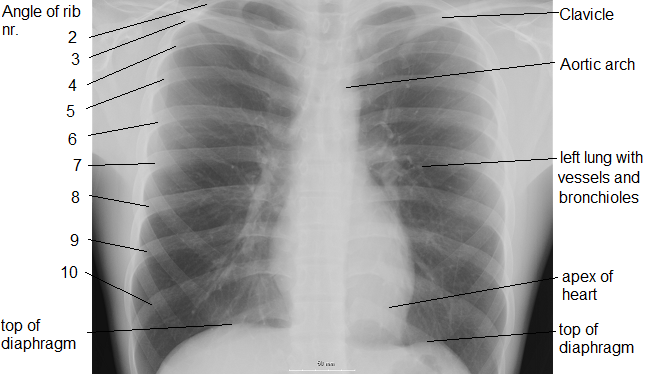

인간의 가슴 부위를 이루는 뼈는 척추, 가슴뼈, 갈비뼈, 빗장뼈 등이다.[6] 흉곽의 뼈는 "흉곽 골격"이라고 불리며, 축 골격의 구성 요소이다. 흉곽은 목과 복부 사이에 있으며, 심장, 폐 등 생체에 중요한 장기를 담는 체부로, 원뿔대 모양의 뜬장 구조로 되어 있으며, 탄력성이 풍부하다. 흉곽 뒤쪽에는 지주가 되는 12개의 척추가 있다. 이 척추를 기점으로 12쌍의 늑골이 앞쪽 아래로 향하고, 측면에서 다시 위로 향하며, 늑연골을 통해 흉골과 연결되어 늑골 케이지(rib cage)를 구성한다.

흉곽의 갈비뼈는 1~12번으로 오름차순으로 번호가 매겨진다. 11번과 12번 갈비뼈는 흉골에 부착되는 연골이 없기 때문에 뜬갈비뼈(부유 갈비뼈)라고 불린다.[6] 8번부터 10번 갈비뼈는 그들의 늑연골이 위의 갈비뼈의 늑연골과 연결되므로 거짓 갈비뼈라고 불린다. 흉곽 뼈는 대동맥과 같은 흉곽 부위의 심장, 폐, 그리고 주요 혈관을 보호하는 주요 기능을 한다.[6]